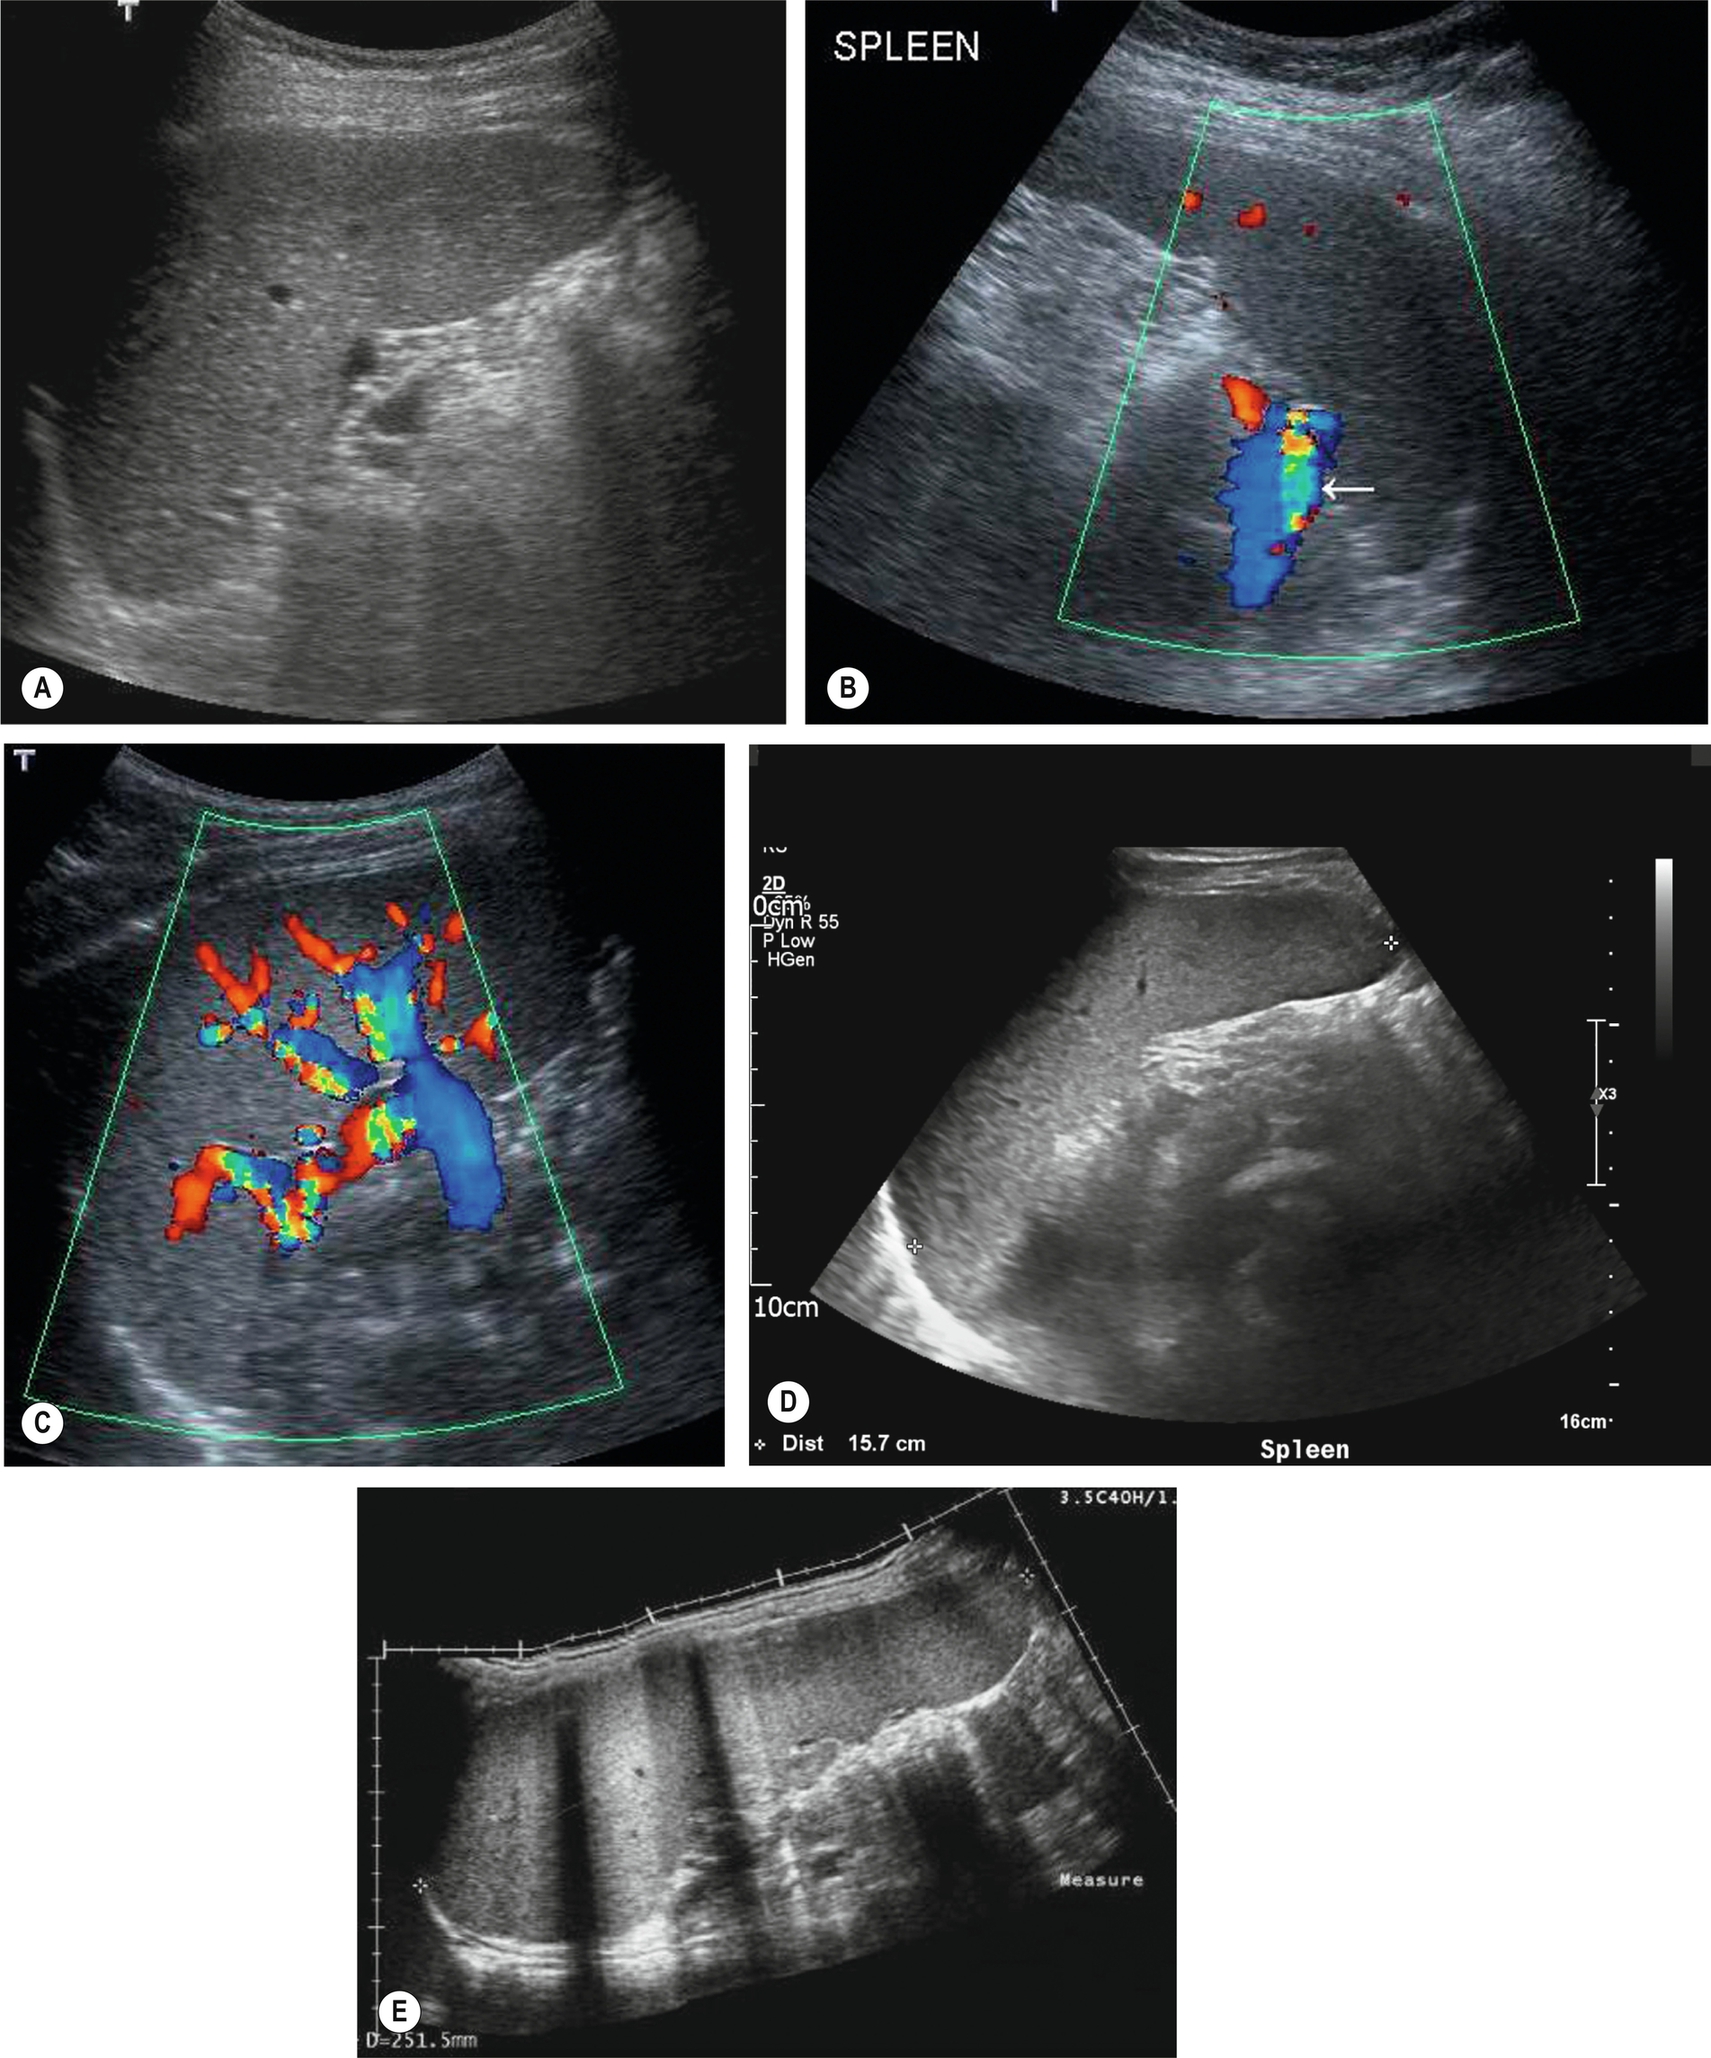

The main splenic artery and vein and their branches may be demonstrated at the splenic hilum (Fig. 5.1A–C). The spleen provides an excellent acoustic window to the upper pole of the left kidney, the left adrenal gland, and the tail of the pancreas.

Measuring the length of the spleen is an adequate indicator of size for most purposes and provides a useful baseline for monitoring changes in disease status which is reproducible by the operator in subsequent scans and comparable to measurements obtained in cross-sectional imaging. Ultrasound is often the modality of choice in monitoring the spleen size because of lack of radiation and good operator reproducibility. A measurement of greater than 12 cm would be considered enlarged in most adults; however, as previously discussed, body size and type can impact the “normal” splenic size range. As the spleen enlarges, it extends downwards and medially. Its inferior margin becomes rounded (Figs. 5.1D–E, 5.2A), and it may extend below the left kidney and into the pelvis.

Although the cause of splenomegaly may not be obvious on ultrasound, the causes can be narrowed down by considering the clinical picture and by identifying other relevant appearances in the abdomen. For example, splenomegaly because of portal hypertension is frequently accompanied by other associated pathologic conditions such as cirrhotic liver changes, varices (Fig. 5.2B), or ascites. In cases of portal hypertension, it is important to assess the splenic vasculature to assess for varices at the hilum.

In the normal spleen, the borders are smooth and regular; however, in rare cases, the diaphragmatic surface of the spleen may appear lobulated or even completely septated. This appearance may give rise to diagnostic uncertainty, and Doppler may help establish the vascular supply and differentiate this from other masses in the LUQ or from scarring or infarction in the spleen.

This is frequently accompanied by portal vein thrombosis and results from the same disorders. The most common of these are pancreatitis and tumor thrombus. Color and spectral Doppler are an invaluable aid to the diagnosis, particularly when the thrombus is fresh and therefore echo-poor. Contrast agents may be administered if doubt exists over vessel patency. Splenic vein occlusion causes splenomegaly, and varices may be identified around the splenic hilum.

Although rare, splenic artery aneurysms are the third most common abdominal aneurysm, with aneurysms of the aorta and iliac arteries having greater incidence.17 On ultrasound, a cystic lesion may be seen around the splenic hilum, and color Doppler can often identify whether this is a vascular structure or whether this is a cystic lesion, such as pancreatic pseudocysts.

Pseudoaneurysm in the spleen occurs in a minority of cases following splenic trauma or in the context of chronic pancreatitis. An echo-free or “cystic” area may be observed, which demonstrates flow on color Doppler. To distinguish between a “true” aneurysm and pseudoaneurysm, the following features should be present in a true aneurysm: focal arterial disruption and inflammation at the location of an irregular vessel wall.17